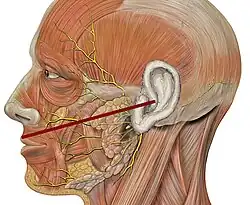

Sa direction correspond à celle d'une ligne horizontale passant par le tragus et le bord inférieur de l'aile du nez. L'artère transversale de la face passe au dessus de ce canal [3].

Schéma anatomique représentant le trajet du canal parotidien